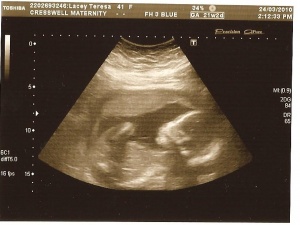

The 17th December 2009 eventually came, we were extremely nervous on that drive to the clinic that morning, I felt so sick with worry.

We were taken into the scan room where I was given an internal scan, after the sonographer had a good look she pointed to a little blob and said there it is and there is only the one, relief to see my blob and even more that there was only the one, the smile on our faces was unreal, she then hit a button and the sound was amazing thump thump thump, there that’s your baby you can hear, I’m afraid that’s when I totally lost it and the tears came and they came hard, I was sobbing with such joy, I wanted to hear that sound every minute of every day until he/she arrived, unfortunately that wasn’t going to be the case and we were given a picture and lots if congratulations and sent on our way.

Teresalsfirstscan Pics 022 17th dec 09.jpg